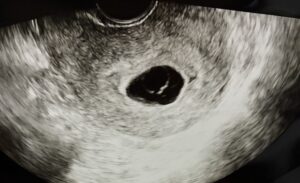

胎嚢は少し大きくなっていて、卵黄嚢も見えました。

でも、赤ちゃん(胎芽)がいない。

稽留流産かもしれません。

受精はしたけれど、うまく育たないかもしれない。1週間後にまた来てください

胎嚢を見たとき、

「赤ちゃん不在」って感じでした。

卵黄嚢まであって栄養も準備されてるのに

住人がいない。